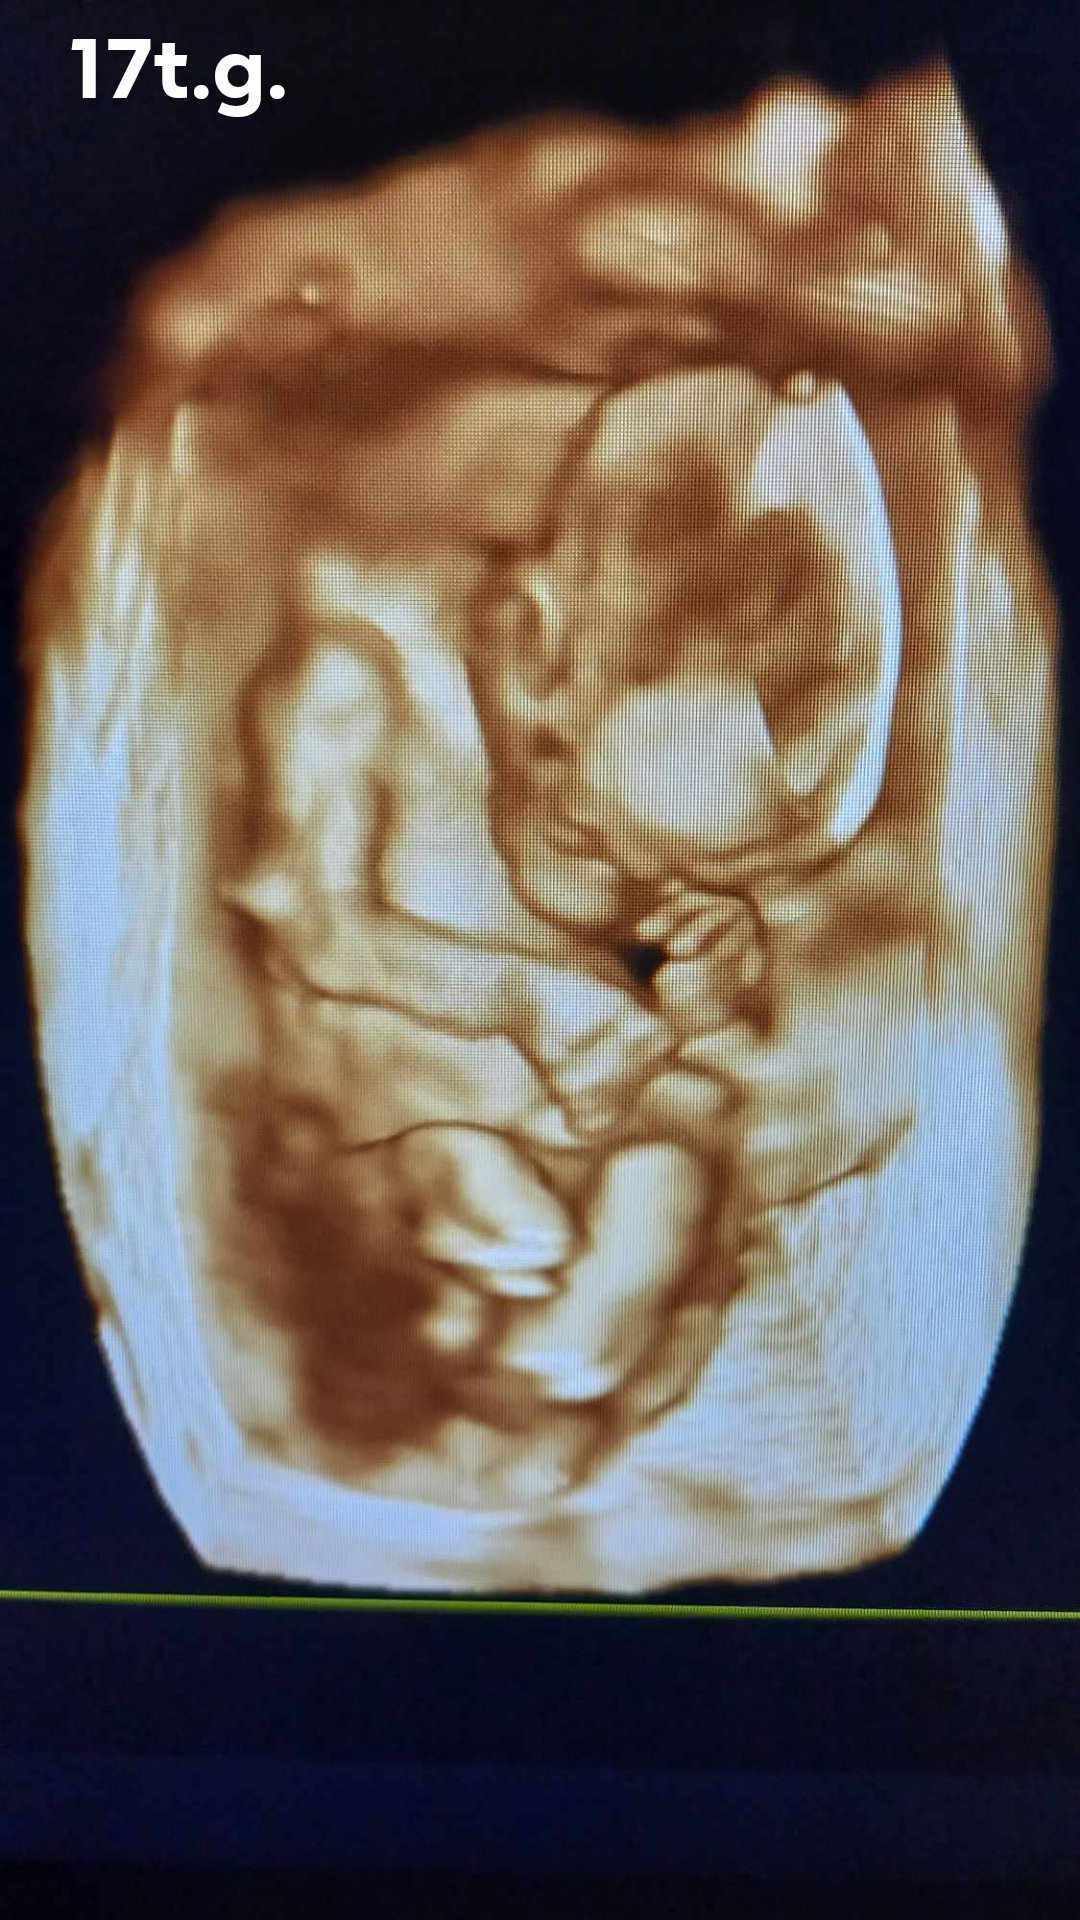

Pozrite si fotky z nášho moderného pracovného prostredia

Naša gynekologická ambulancia je vybavená modernou technikou a poskytuje pacientkom príjemné a komfortné prostredie pre všetky druhy vyšetrení a konzultácií.